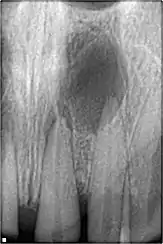

- À la suite de la nécrose de la dent concernée. La nécrose se fait le plus souvent à la suite d'une carie non traitée. Elle peut également survenir à la suite d'un choc sur la dent, parfois plusieurs années après. Dans ce cas la nécrose se fait sans douleur, et les seuls signes sont radiographiques (radioclarté apicale).